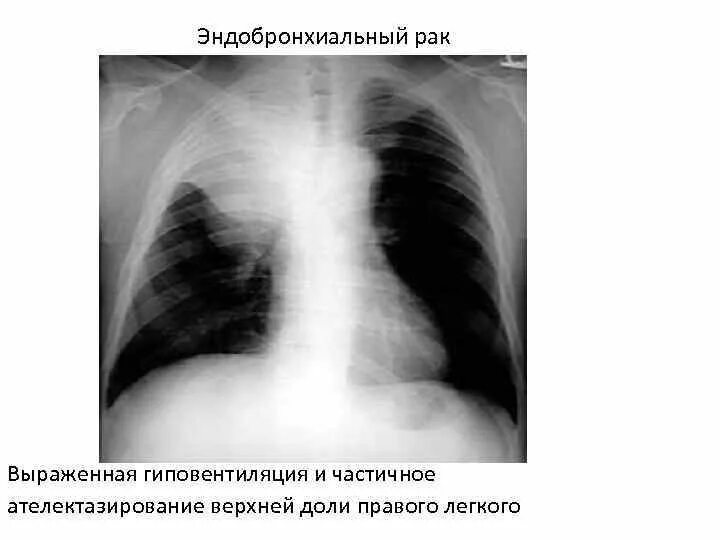

Лучевая при раке легких